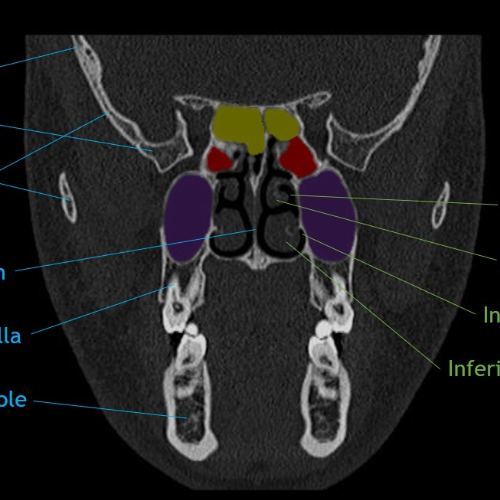

CaseStacks.com - MS1 Anatomy Coronal Face CT Anatomy

www.casestacks.com

www.casestacks.com

coronal casestacks